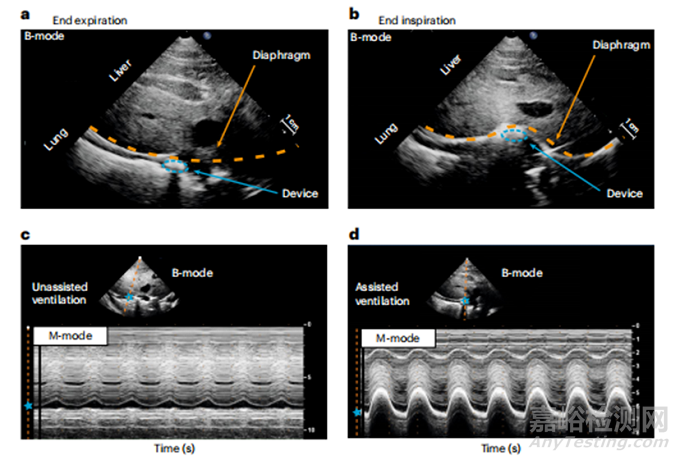

在動物體實驗中,研究團隊模擬了動物的各類呼吸功能不全(如通過麻醉誘導呼吸抑制,通過切斷膈神經(jīng)誘導膈肌癱瘓)。通過超聲(b型)斷層成像顯示PAM對隔膜的推動,監(jiān)測其位移情況。(圖2a,b)。為了量化設備和橫膈肌的運動,采用了M型模式超聲,該模式適用于進行運動分析。圖2c,d記錄了隔膜每次呼吸時的位移變化,不對PAM加壓時,隔膜位移為0.37厘米。加壓后,增加至1.92厘米。

圖2 a,b.隔膜的二維視圖。a為松弛狀態(tài),b為加壓狀態(tài)。c.無輔助通氣時的橫膈膜運動狀態(tài)。d.有輔助通氣時的橫膈膜運動狀態(tài)。橙色虛線表示隔膜,藍色虛線圓圈表示PAM橫截面,藍色星形表示隔膜的空間位置。